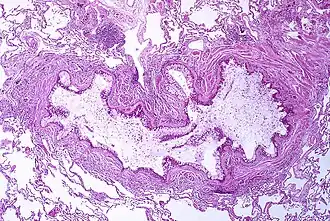

Pathofysiologie

Astma is het resultaat van een chronische ontsteking van de luchtwegen die leidt tot een verhoogd samentrekkingsvermogen van de omringende gladde spieren. Dit is een van de factoren die leidt tot aanvallen van luchtwegvernauwing en de klassieke symptomen van een piepende ademhaling. De vernauwing is doorgaans reversibel met of zonder behandeling. Soms veranderen de luchtwegen zelf.[16] Veelvoorkomende veranderingen in de luchtwegen zijn een toename van eosinofielen en verdikking van de lamina reticularis. De gladde spieren van de luchtwegen kunnen blijvend worden vergroot en het aantal slijmklieren kan toenemen. Andere celtypen die daarbij betrokken zijn, zijn onder meer: T-lymfocyten, macrofagen en neutrofielen. Er kunnen nog meer componenten van het immuunsysteem bij betrokken zijn, onder andere: cytokinen, chemokinen, histaminen en leukotriënen.[42]